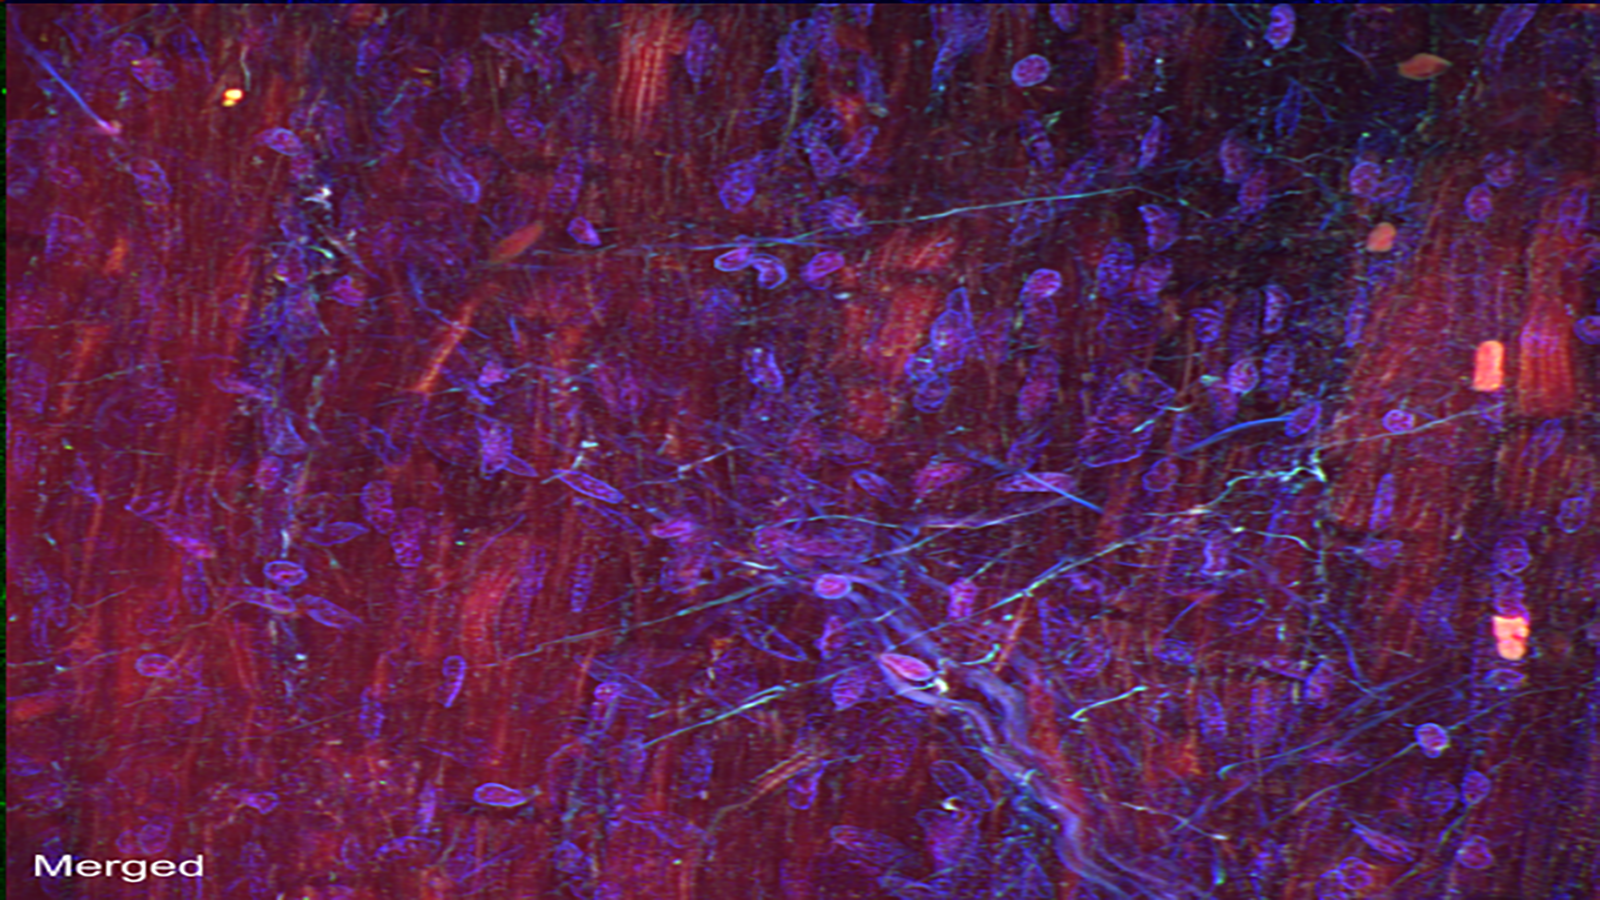

Autofluorescence image capturing heart cells (red), nuclei (blue), and dense fibers of the heart (green), courtesy of Dr. Seth Currlin at University of Florida

An autofluorescence image of cells that make up the heart/cardiac muscle, from Dr. Seth Currlin of University of Florida